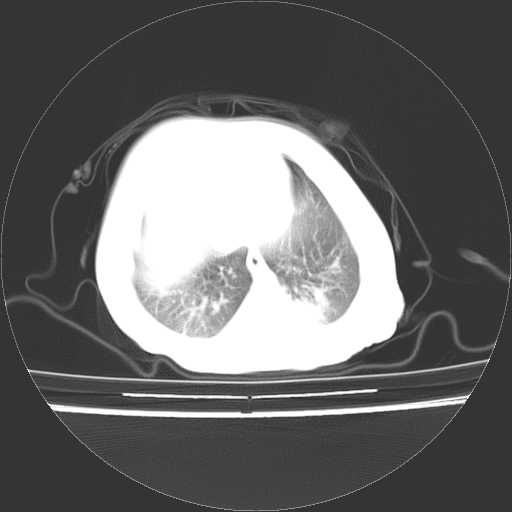

以下是引用影像之路在2009-5-8 15:46:00的发言:[br]1)胸廓畸形。2)考虑两肺感染性病变,并右肺上中叶肺不张;建议抗炎治疗后复查。3)胸腺肥大。4)前上中纵隔占位性病变待排;建议追踪复查。

以下是引用随光逐影在2009-5-8 8:33:00的发言:[br]1)胸廓畸形。2)考虑两肺感染性病变,并右肺上中叶肺不张;建议抗炎治疗后复查。3)胸腺肥大。4)前上中纵隔占位性病变待排;建议追踪复查。

以下是引用余辉在2009-5-8 8:44:00的发言:[br]鸡胸,胸腺肥大,双肺感染性病变,结合病史支原体肺炎可能性大